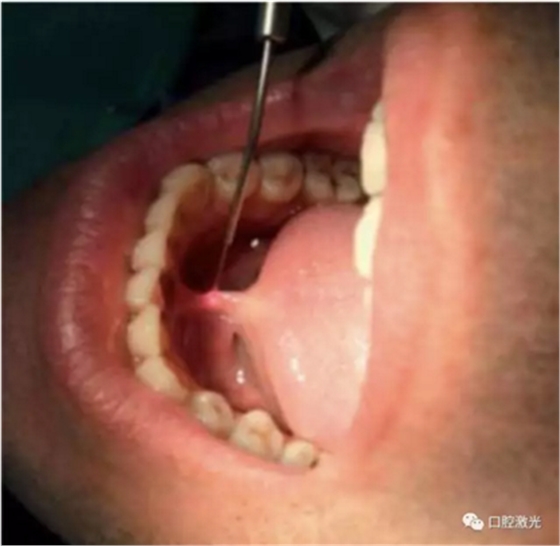

利用口腔激光进行系带整形需要实施局麻,可以使用2%利多卡因。采用300um激光光纤,设置功率为4W。激光光纤垂直和水平作用于系带上,从而使系带黏膜得到很好的分离。通过这种方式,系带在水平方向上可以很容易获得一个较深的切口。系带整形后的伤口是呈菱形,整个过程大约4,5分钟。在任何情况下,都不需使用缝针。可以使用冰敷的方式降低组织温度,控制组织坏死的风险。术后复检的时间为1周、3周和3个月。复检时,包括疼痛,出血,水肿,疤痕组织形成以及伤口愈合的特征都应得到有效的评估。

在术中和术后恢复期间,都没有观察到出血的情况。术后没有发现明细的疼痛和水肿。术后三周时,口腔黏膜完全恢复健康,没有形成疤痕组织。在长期跟踪观察中,口腔黏膜的色泽和形态一直处于正常状态。